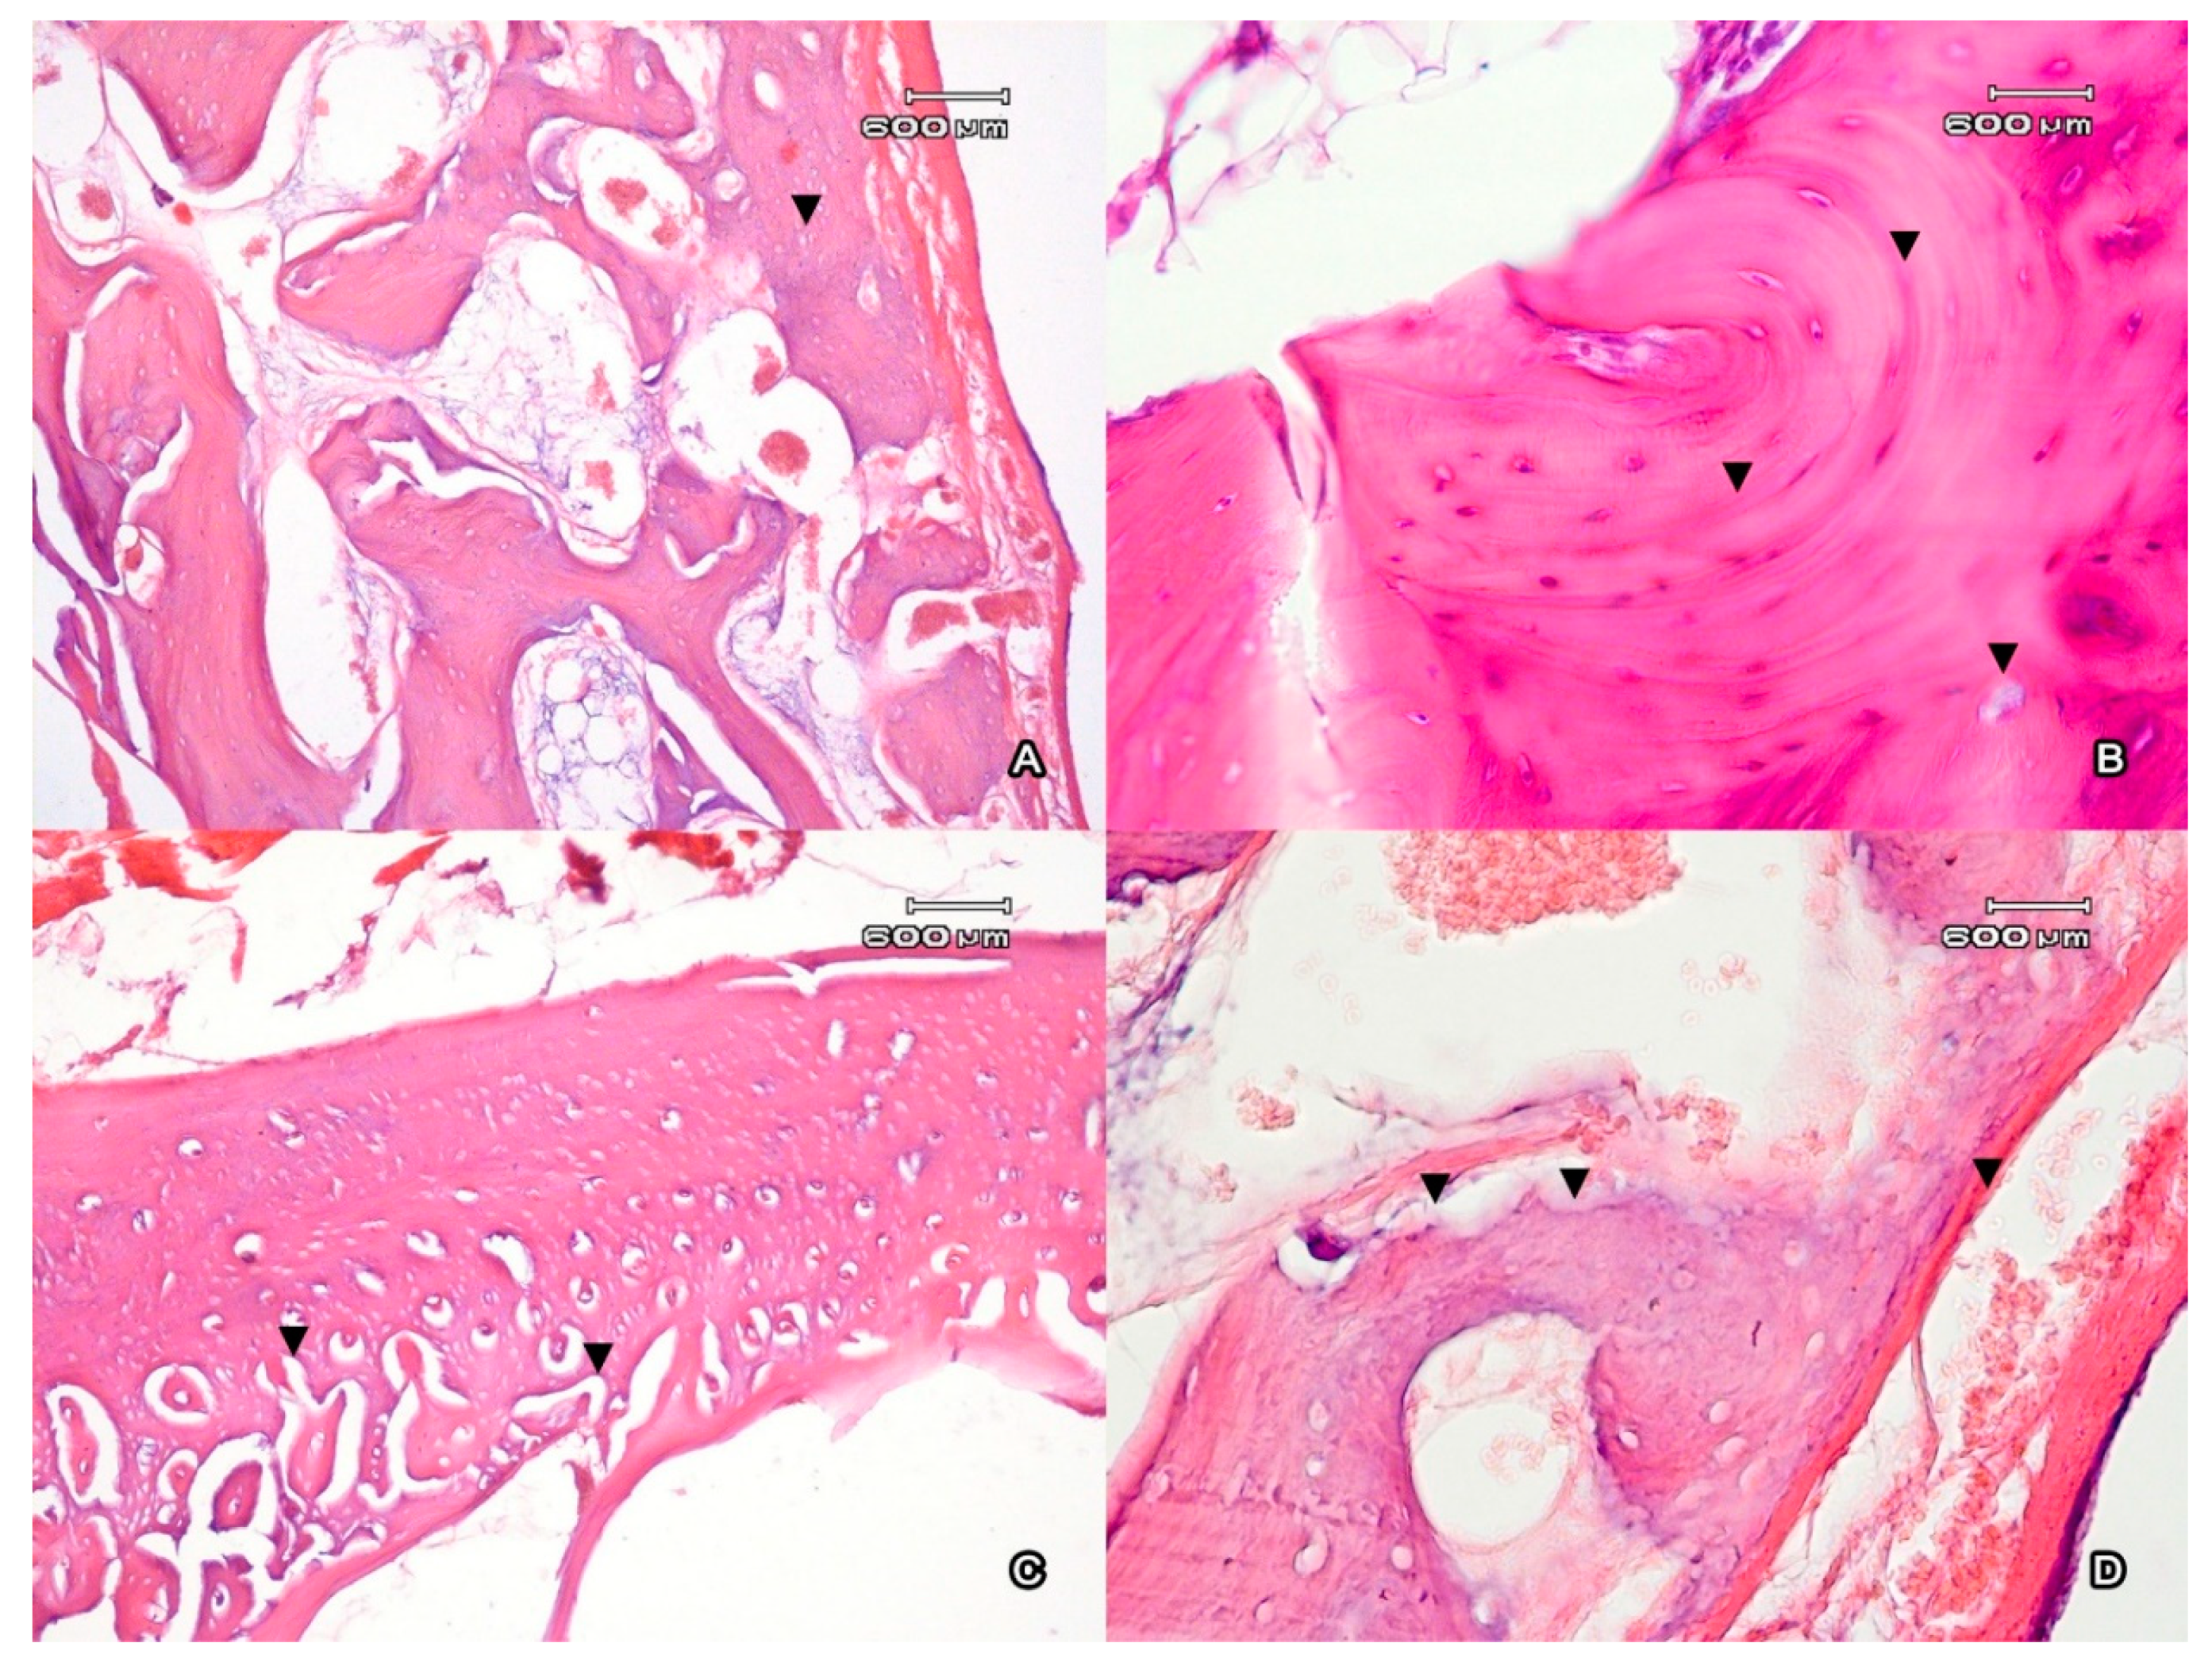

In the buccal area of the alveolar arch, the cortical plate of the intact tooth was presented by a compact bone that consisted of osteons; each of them contained from 3 to 10 rows (Figure 2A). The bone surface contained numerous basophil lines of the fusion and foci of periosteocytic resorption (Figure 2B). Uneven thinning of the cortical plate on the major part of the alveolar socket was observed. In places where the minimum bone thickness was observed, the highest volume density of the eroded surface formed with osteoclasts was registered. On the intact side, the volume density of the eroded surface was 11.3 ± 0.6%; on the side of the graft, it was 15.7 ± 1.2% (at p < 0.05). The eroded surface was covered with osteoid with no signs of mineralization (Figure 2C). The thickness of the osteoid on the intact side was 2.2 ± 1.6 µm, and on the side of the graft it was 3.1 ± 2.6 µm; the difference was insignificant at p ˃ 0.05. In the area of the alveolar fossa, there were lacunas of resorption on the medullar part of the trabecula of the bone (Figure 2D). The medullar part of the bone tissue was filled with loose fibrous connective tissue that contained capillaries.

Figure 2.

The cortical plate (A) of the incisor alveolus represented by the compact bone (▼). Magnification ×100. The compact bone (B) contains signs of active transformation (basophil lines of the (▼)). Periosteocytic resorption (▼). Magnification ×400. The external surface of the alveolar edge (C) of the mandible next to the area of implantation of CaSiO3/HAp. The number of osteons increased close to the alveolar lumen in the compact bone (▼). Magnification ×100. (D) The stripe of osteoid on the bone surface facing the alveolar fossa (▼). Lacunas of absorption on the medullar part of the trabecula of the bone (▼). Magnification ×400. Ehrlich’s hematoxylin and eosin stain.

After the injection of CaSiO3/HAp in the area of the tooth extraction, a complete restoration of the bone outside the alveolar fossa was registered. Morphologically, the area of the exposure of the graft was characterized by the formation of lamellar compact bone that formed the cortical part of the socket (Figure 3A). There were no areas of resorption registered on the medullar part of the trabeculae, unlike the intact tooth. The proliferation of the fibrous tissue spreads on the medullar part of the bone. There were single foci of periosteocytic resorption observed. The mean thickness of the cortical plate was uniform and equal to 293.9 ± 0.9 µm. In the periosteum, there were foci of neoangiogenesis registered that were presented as full-blooded capillaries. There were vast areas of reactive fibrosis, which was visually characterized by an increase in the mean thickness of the periodontal ligament (Figure 3B).

Figure 3.

(A) The cortical cross-section plate (●) of the walls of the alveolar fossa of the incisors after CaSiO3/HAp implantation. The proliferation of fibroreticular tissue with the spread on the medullar part of the bone (▼). Magnification ×100. (B) Internal surface of the alveolar edge of the mandible next to the area of the CaSiO3/HAp implantation. An increase in the thickness of the periodontal ligament (▼). Magnification ×100. (C) Periosteum of the internal surface of the alveolar fossa, the filling of the osseous defect with osteoid (•).The highest number of osteons was observed close to the internal surface of the alveolar fossa (▼). Magnification ×100. (D) The ossification of the implant in the lumen of the alveolar fossa (•). Filling of the cavities with loose fibrous connective tissue with angiomatosis (▼). Magnification ×100. Ehrlich’s hematoxylin and eosin stain.

In the compact bone that surrounds the alveolar socket after the filling with powder graft, the number of osteons increased close to the alveolar lumen, as well as on the intact side (Figure 3C). The periodontal ligament was the source of the newly generated connective tissue in the graft because it was rich in the stem cells that transformed into the endotheliocytes and pericytes of the newly formed vessels [31]. Further, the pericytes in bone tissue are capable of transformation into osteoblasts [37], and this fact can be interpreted as an osteoinductive phenomenon for a disperse CaSiO3/HAp biocomposite as a structural powder. Ions of calcium and phosphate are osteoinductive factors for mesenchymal cells that stimulate their transformation into osteoblasts and contribute to the genesis of new bone tissue [38]. The graft acted as a component of a regenerative process of bone tissue. Granulating tissue penetrated the material of the graft, organized it, and fixed it to the periodontium (Figure 3D). This peculiarity of CaSiO3/HAp was considered to be an osteoconductive factor. Along with this, the majority of the authors believe that it is necessary to prevent the development of fibrous tissue in the area of the graft.

The periosteum of the external and internal surface of the alveolar ridge was presented as a thin layer with poor vascularization. It differs from the alveolar periodontal ligament that contacts the alveolar periosteum. At the same time, the material that lines the alveoli from the inside contains an increased number of full-blooded vessels. The regional hyperemia of the spongious bone adjacent to the alveoli is observed. An increased number of full-blooded vessels (Figure 3B) represents it. This indicates an important role of angiogenesis in the regulation of structural homeostasis in this region in the mandible. At the same time, the blood vessels of this section of the alveolus have a wide lumen and a thin wall with no adventitia. In the graft samples, there was a tendency toward a thinning of minor parts of areas of cortical plate in the compact bone that lines the alveolar socket (from 142.3 to 274.1 µm). The appearance of the massive trabeculae of the spongious bone adjoining the cortical plate in the area of the alveolar socket was observed. The thickness of the trabeculae of the spongious bone was 52.1 ± 3.9 µm, and in the area of implantation it was 68.5 ± 6.5 µm (p < 0.05) (Figure 3A).